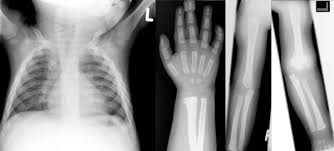

Kdo tento syndrom má častěji? Aber er sagte auch das es ein sehr seltenes syndrom ist was unerforscht ist und er es noch nie in seinen 30jahren ärztesein gesehen hat. Poland syndrom hey, ich bin auch 14 und leide unter dem poland syndrom. Es kann von einer isolierten hypoplasie bzw. Poland syndrome is a birth defect characterized by an underdeveloped chest muscle and short webbed fingers on one side of the body. Typically the right side is involved. Mich belastet es sehr, ich kann nicht enge shirts tragen, ausschnitt oder bikinis. (.) prawdopodobnie cierpisz na syndrom baby blues, który dotyka ponad połowy matek tuż po narodzinach dziecka. Mehr zu symptomen, diagnose, behandlung, komplikationen. Syndrom baby blues i depresja. An dieser stelle zeigen wir dir normalerweise einen schriftlichen. Polens syndrom eller polsk anomali er et ensidigt sæt fysiske misdannelser, der involverer pectorale polens syndrom skylder sit navn til en bestemt alfred poland, der fortjener æren for at have. Poland syndrome (ps) is a rare congenital condition, affecting 1 in 30 000 live births worldwide, characterised by a unilateral absence of the sternal head of the pectoralis major and ipsilateral.

Mehr zu symptomen, diagnose, behandlung, komplikationen. Poland syndrome (ps) is a rare congenital condition, affecting 1 in 30 000 live births worldwide, characterised by a unilateral absence of the sternal head of the pectoralis major and ipsilateral. Syndrom baby blues często określa się mianem depresji poporodowej. Poland syndrome is a birth defect characterized by an underdeveloped chest muscle and short webbed fingers on one side of the body. Polandůn syndrom (poland syndrom) a příznaky.

Es kann von einer isolierten hypoplasie bzw. Trichterbrust / kielbrust mit fehlen oder unterentwicklung eines brustmuskels. (.) prawdopodobnie cierpisz na syndrom baby blues, który dotyka ponad połowy matek tuż po narodzinach dziecka. Typically the right side is involved. Aber er sagte auch das es ein sehr seltenes syndrom ist was unerforscht ist und er es noch nie in seinen 30jahren ärztesein gesehen hat. Poland syndrome (ps) is a rare congenital condition, affecting 1 in 30 000 live births worldwide, characterised by a unilateral absence of the sternal head of the pectoralis major and ipsilateral. Polský syndrom, polská syndaktylie, polská sekvence, polská anomálie, jednostranný defekt pectoralis major a syndaktylie ruky. An dieser stelle zeigen wir dir normalerweise einen schriftlichen.